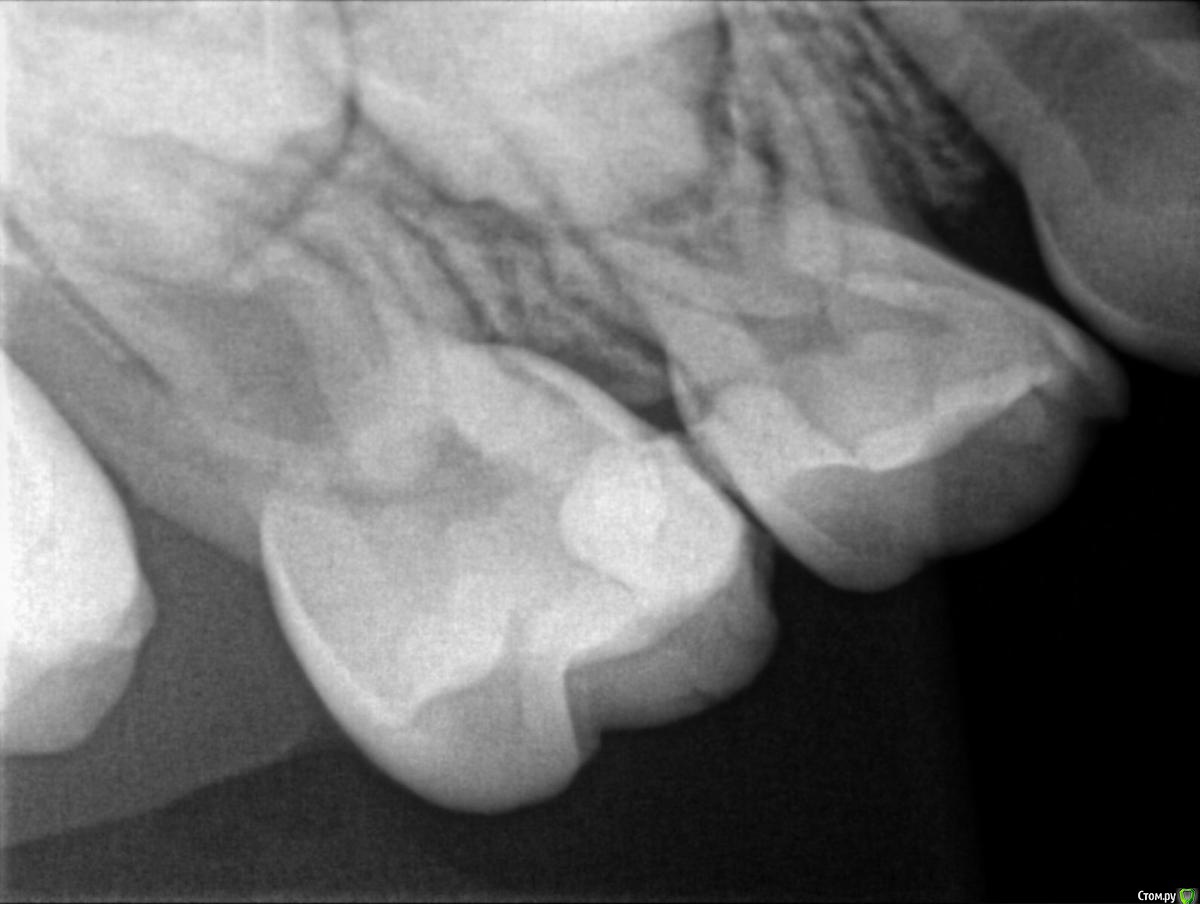

Пошли к врачу, сделали рентген и на рентгене видно что начал образовываться кариес почти на всех молярах, либо под пломбами, либо на стыке зубов. Так как зубы уже леченые доктор говорит что лечить дальше смысла нет, пломба держаться не будет, выпадет снова, предлагают ставить коронки сразу на все моляры, а зуб где уже большая пломба (зуб I на ренгене) просто удалить (не болит) и поставить space mantainer + удалить зуб А.

На наш НЕпрофессиональный взгляд, пломбы не такие уж большие чтоб закатывать в коронки, у старшего сына была аналогичная вообщем то ситуация и когда были в россии да, пломбы вываливались, на их место ставили новые, иногда удаляли нерв, но в итоге до смены зубов все дошло без удаления.

На всякий случае прикрепляю снимки, буду рад услышать мнение.